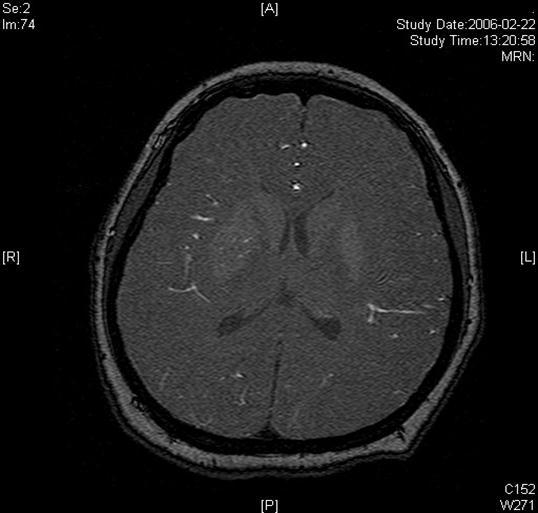

A twenty-nine-year-old female was admitted in Feb, 2006 because of episodic left limb numbness and weakness for half a year. The duration of the episode lasted for a few minutes, seldom over ten minutes. There was an attack every several days. She denied special medical history. She did not live in the pandemic area of Leptospirosis. Her blood pressure was 110/65mmHg and body weight was 51 kilograms. Physical examination found no abnormality. Magnetic resonance angiogram (MRA) (Feb 22) showed severe stenosis in the M1 segment of right MCA. In the source images of MRA, an oval area of abnormal signal in the right basal ganglion was found (Figure 1). Blood routines, coagulation tests, blood biochemistry tests, and C-reactive protein level were normal. The anti-nuclear antibody (ANA), anti-extractable nuclear antigen (ENA) antibodies, and anti-neutrophil cytoplasmic antibodies (ANCA) were negative. Serologic test for Syphilis was negative. Blood sedimentation rate (ESR) was 20 mm/h, and the level of anti-streptolysin O microtitration test (ASO) was 395 IU/ml (0-200 IU/ml). Digital subtraction angiography (DSA) detected severe stenosis (95%) in M1 segment of the right MCA, and the distal blood flow was compromised (Figure 2). The patient was given aspirin 100mg/d, clopidogrel 75mg/d and atorvastatin 20mg/d since Feb 26. Due to the finding of high ASO level, she was given penicillin (4 million IU, bid) for a week. Because of disagreement between the consulting physician and the interventional radiologist, her angioplasty and stenting was delayed till Mar 21 on her request. During the waiting time, her attacks did not reduce. Before the operation, besides the combination of aspirin and clopidogrel, subcutaneous low molecular weight heparin (LMWH) (5000U, q12h) was given for 5 days. After a complete diagnostic evaluation of the blood vessels with DSA, stenting was performed with a stainless steel stent 2.75 mm in diameter by 1.5 cm in length (PC, Abott Company) at the presure of 7 atm. No compromise of perforating branches was found and residual stenosis was less than ten percent on angiography (Figure 2).

Figure 1.Lesion in the right basal ganglia displayed in the source image of MRA